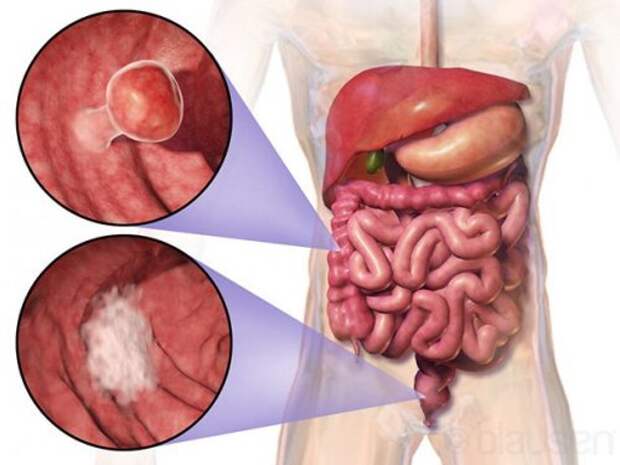

1. Отделы пищеварительной системы подвержены образованию злокачественных опухолей чаще, чем какие-либо другие органы нашего тела. По статистике больше всего от рака умирают пациенты, заболевания которых связанны именно с системой пищеварения.

1. Отделы пищеварительной системы подвержены образованию злокачественных опухолей чаще, чем какие-либо другие органы нашего тела. По статистике больше всего от рака умирают пациенты, заболевания которых связанны именно с системой пищеварения.